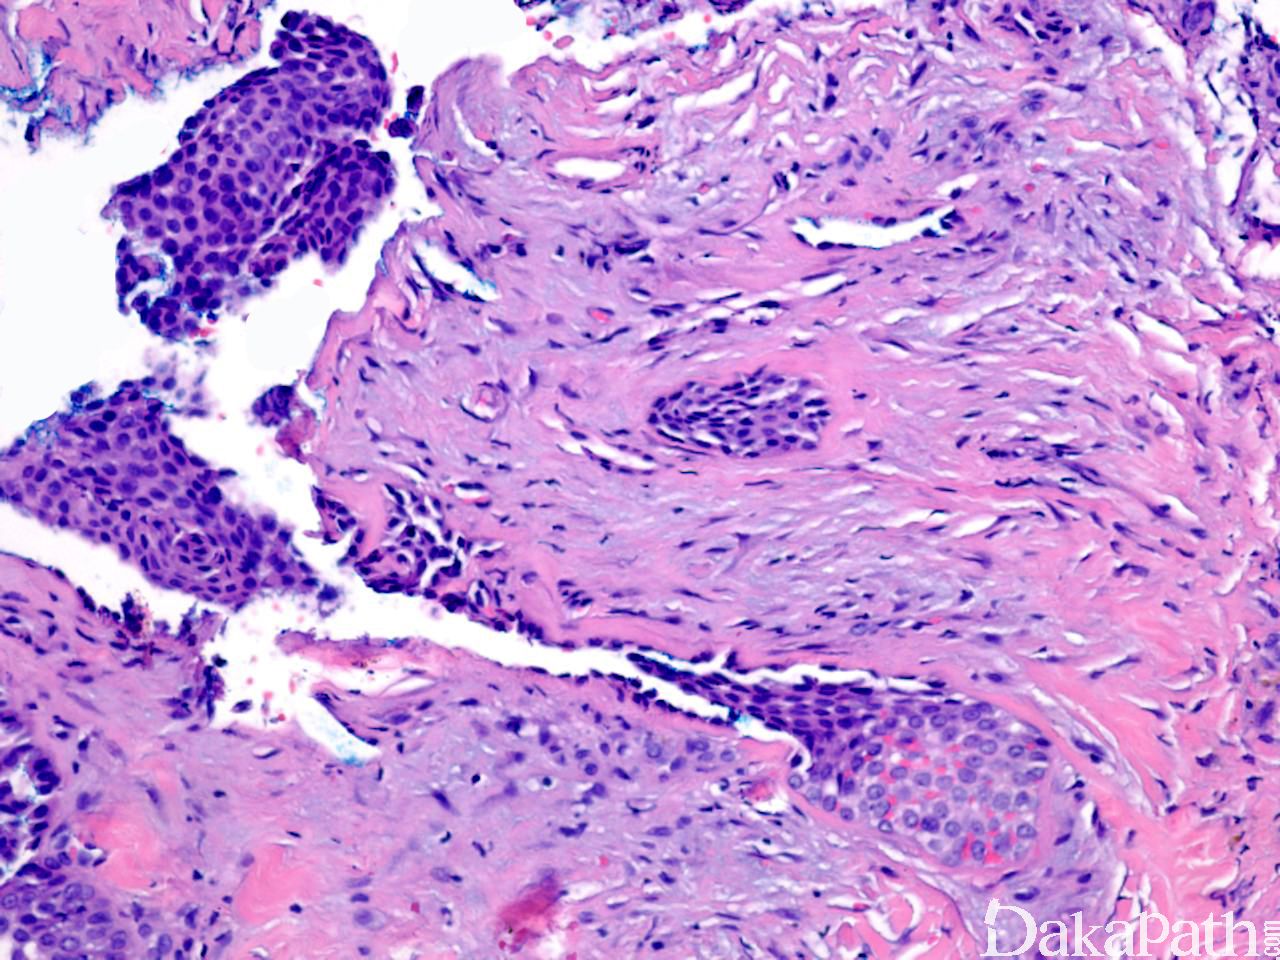

常位于真皮内,较大肿瘤可累及皮下组织,表现为界限清楚的结节,主要为实性,也可为囊实性;

镜下见一致的嗜酸性细胞或糖原丰富透亮大汗腺样细胞增生,形成巢状或小叶状结构;

整个病变均可见到导管结构,一些导管扩张形成囊性区域,囊内充满粉染分泌物;

导管和囊性结构内衬立方形导管细胞或柱状分泌细胞,核形规则,染色质轻度增多,核分裂象少见;

某些区域可见鳞状分化,甚至角化珠形成;

间质纤维化,可伴有广泛的透明变性;

部分病例间质富含血管。